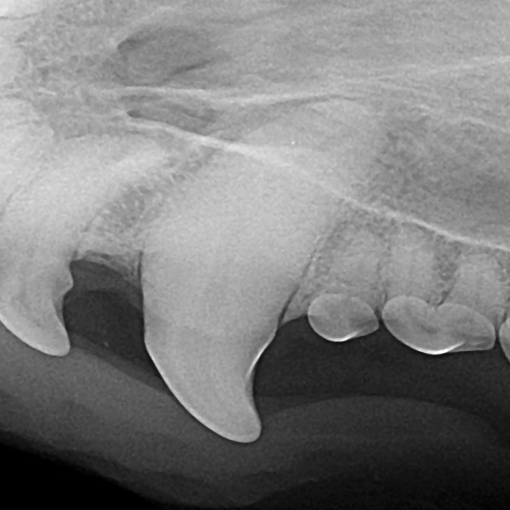

Example of a fractured canine tooth in a dog:

Before: